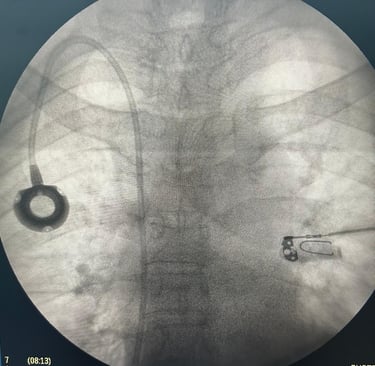

ACESSOS PARA QUIMIOTERAPIA E DIÁLISE

Pacientes que realizam quimioterapia ou diálise precisam de acessos vasculares bem planejados e monitorados para garantir segurança e eficácia no tratamento. Um acompanhamento especializado pode evitar complicações e melhorar a qualidade de vida.

• Tratamento oncológico com quimioterapia

• Doença renal avançada com necessidade de hemodiálise

• Procedimentos que exigem cateteres de longa duração